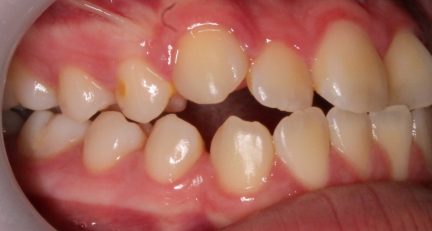

Classe III, articulé postérieur, articulé antérieur, occlusion bout-à-bout, béance, arcades asymétriques, déviation de la ligne médiane mandibulaire, chevauchement, rotations, espacement

État initial